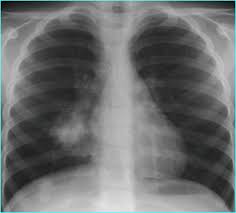

►XQ Phổi : đây có thể coi là xét nghiệm cơ bản tầm soát ung thư giai đoạn sớm, XQ phổi có thể gợi ý tổn thương ngi ngờ ung thư như vị trí khối u, kích thước, mức độ lan rộng…từ đó giúp bác sĩ định hướng các xét nghiêm cần làm thêm để chẩn đoán xác định.